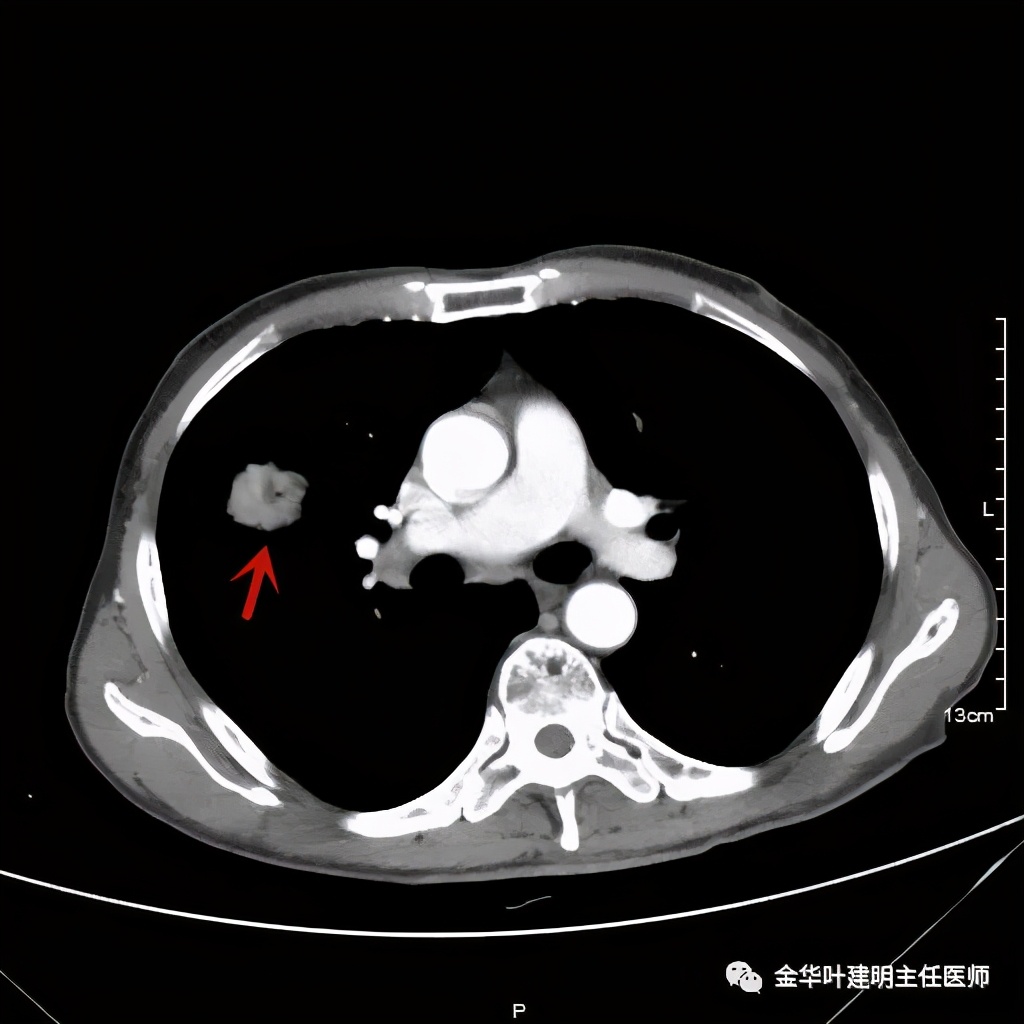

上图示纵隔窗实性

上图示纵隔窗密度不均

上图示纵隔窗病灶有膨胀性,内部有强化较明显的条索状(新生血管?)

上图示纵隔窗病灶表面欠平整,中间有小空洞,密度不均,局部似有坏死(空洞旁边)